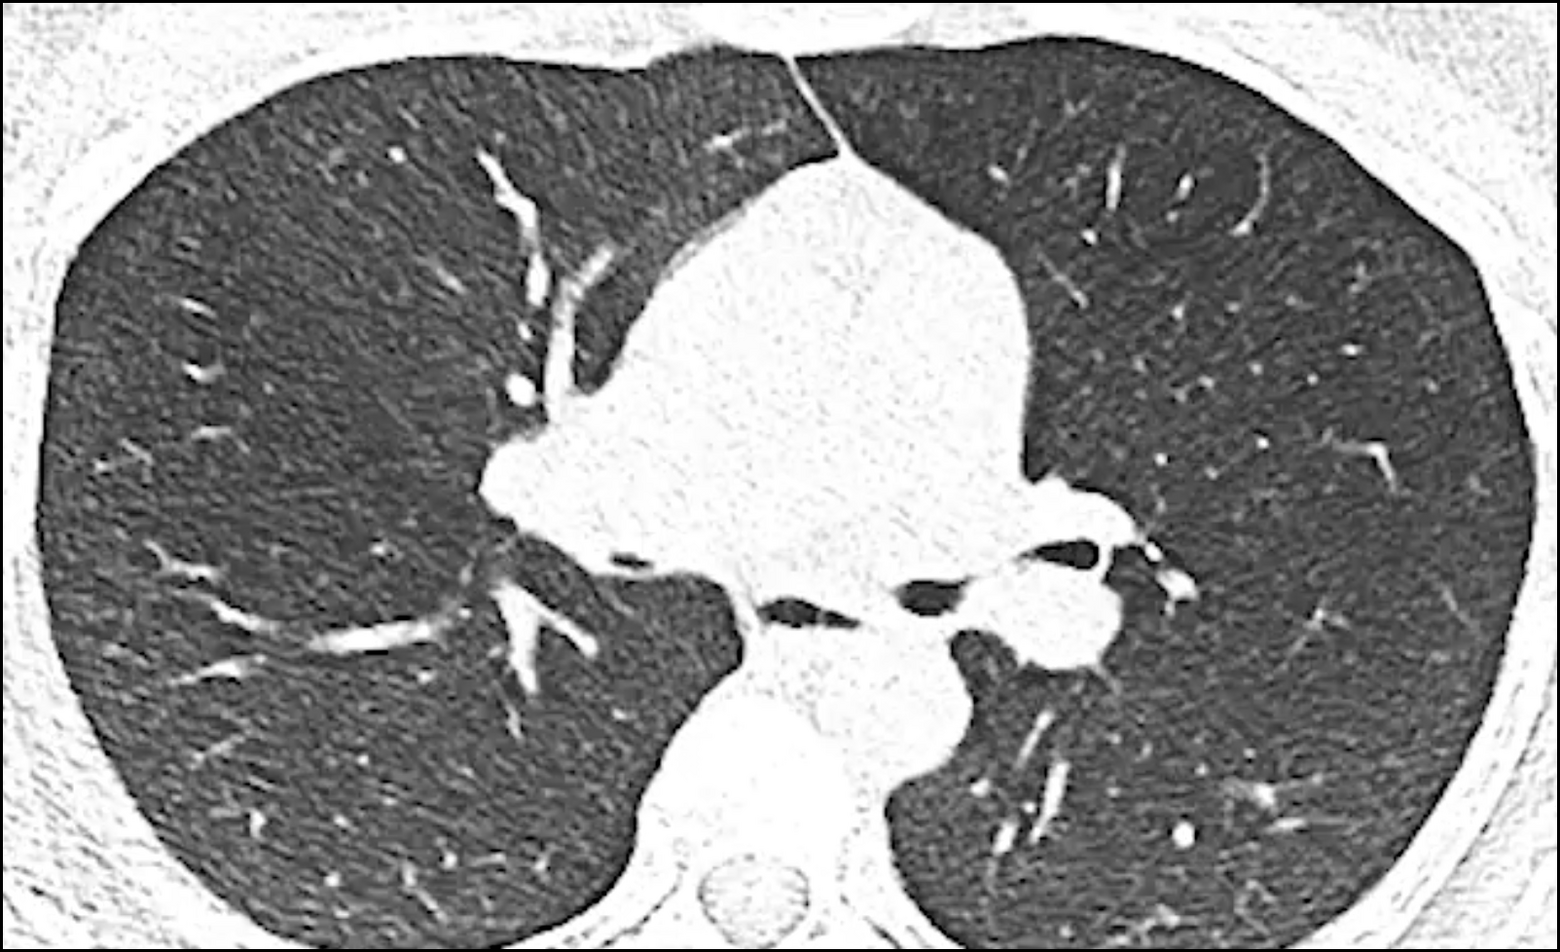

Données du CT-Scan

Les données du CT-Scan du patient sont le point de depart pour créer un stent NOVATECH® 3D.

Sur la base des images du CT-Scan des voies aériennes du patient, fournies par le médecin par transfert par serveur ou CD, une reconstruction virtuelle des voies aériennes du patient est réalisée.

Implantation réussie d’un stent NOVATECH® 3D dans un patient souffrant d’une bronchomalacie dans la bronche droite.

Images gracieusement fournies

par le Dr Daniel Franzen, Zurich.